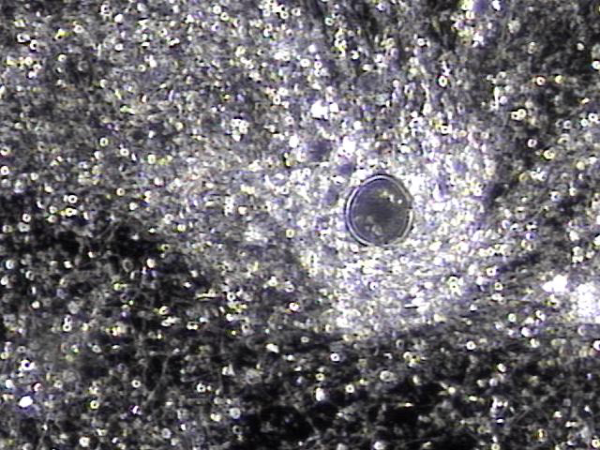

전립선과 정낭과 정관 그리고 사정관 등에서 전립선의 표적 치료후 배양 검사를 하기위해 배출된 결석과 혈정액의 현미경 학적 사진입니다.

Microscopic image of stones and hematospermia discharged from the prostate, seminal vesicles, vas deferens, and ejaculatory ducts following targeted prostate therapy, collected for culture testing.